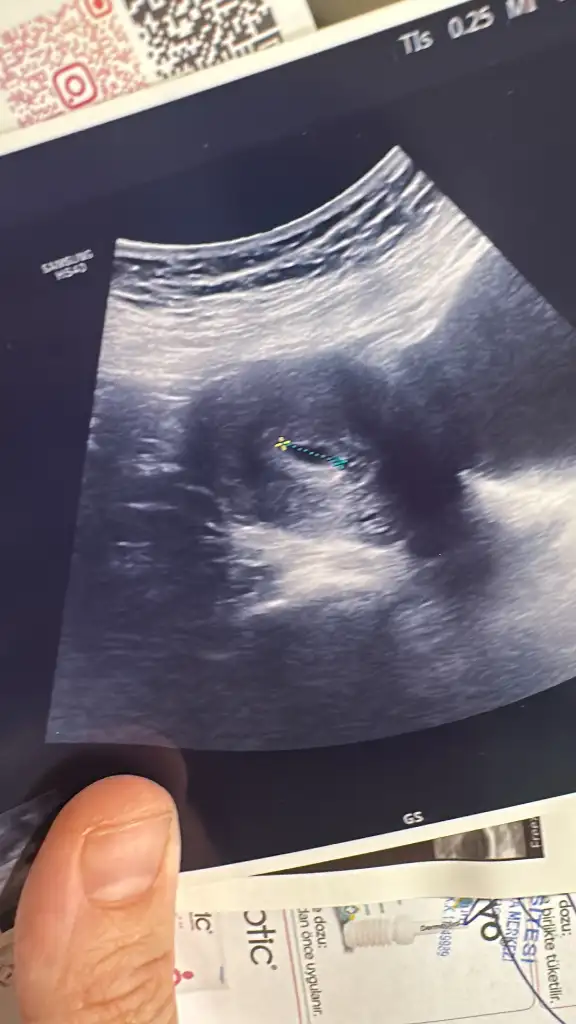

Benim çok ilginç oldu öğrenmem hastanede staj için akciğer filmi çektirecektim ki o gün hesaplayınca adet günümün iki gün geçtiğini fark ettim doktorum bunu belirt hatasız bir kere çekerlerse bir şey olmaz dedi söyledim çekmediler gebelik testi istediler sinirlendim yaptım öğleden sonra gel çekeriz dediler sonuçla bir baktım ki iki saat sonra 332 çıktı sonra iki gün sonra hcg 746 oldu dış gebelik olabilir dedi doktor kendi doktorum yok diye gitmiştim neyse bugün keseyi gördük şükür sanırım bu gruptayım yaşım 39 üçüncü çocuk sat 9 Mayıs ekler misiniz😍

Eklentiler

• D3299AB7-D343-4A4C-A2DA-772460F9A144.webp

D3299AB7-D343-4A4C-A2DA-772460F9A144.webp

29,7 KB · Görüntüleme: 46